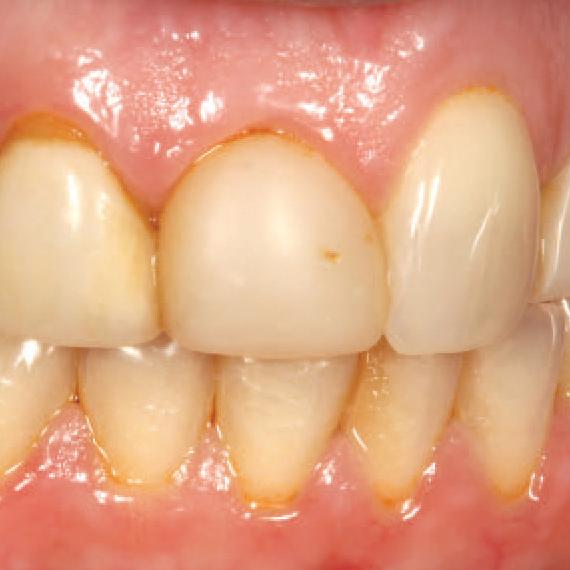

A significant number of people are unhappy with their smile, which has a considerable psychosocial impact. Although many seek cosmetic dental treatment, costs, fear and duration of total treatment are often barriers to the patients. Nevertheless, many could benefit from small and subtle changes to their teeth. With simple direct and freehand techniques, quick but significant results can be obtained that ultimately greatly improve the overall smile aesthetics.

The restoration of abfractions in the anterior area is important for aesthetic appearance especially in patients with high smile lines. Moreover, restoring abfractions strengthens the cervical area of the tooth, prevents further loss of enamel and ameliorates unpleasant sensitivity.

Black triangles and diastemas can cause entrapment of the food and accumulation of bacteria, which leads to gingivitis and ultimately periodontitis. By eliminating the black triangles and diastemas with composite bonding, the dentist not only improves the aesthetics, but also protects the long-term health of the periodontal tissues.

Worn canine cusp restoration is of special functional importance. Creating functional canine guidance with a minimally invasive composite addition to the canine cusp will protect the posterior teeth during lateral movements of the jaw. Incisal wear restorations return the youthful appearance to the smile and prevent further loss of enamel and exposure of the dentinee.

Restoring incisal wear and closing diastema with G-aenial A’CHORD. Courtesy of: Dr Aleksandra Slacan, Poland

Reshaping of teeth and diastema closure with G-aenial A’CHORD. Courtesy of: Dr Andres Silva, Spain